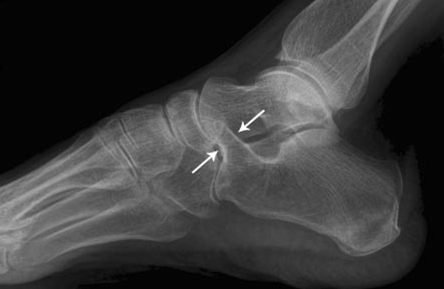

Qu’est-ce qu’une tarsal coalition ? Que peut-elle provoquer ?

Anomalie congénitale non symptomatique étant la fusion du calca avec talus ou du calca avec naviculaire.

Cela peut créer des entorses à répétition.

Qu’est-ce que l’anteater sign ?

En scanner fenêtre osseuse, c’est la fusion entre le calca et le naviculaire.